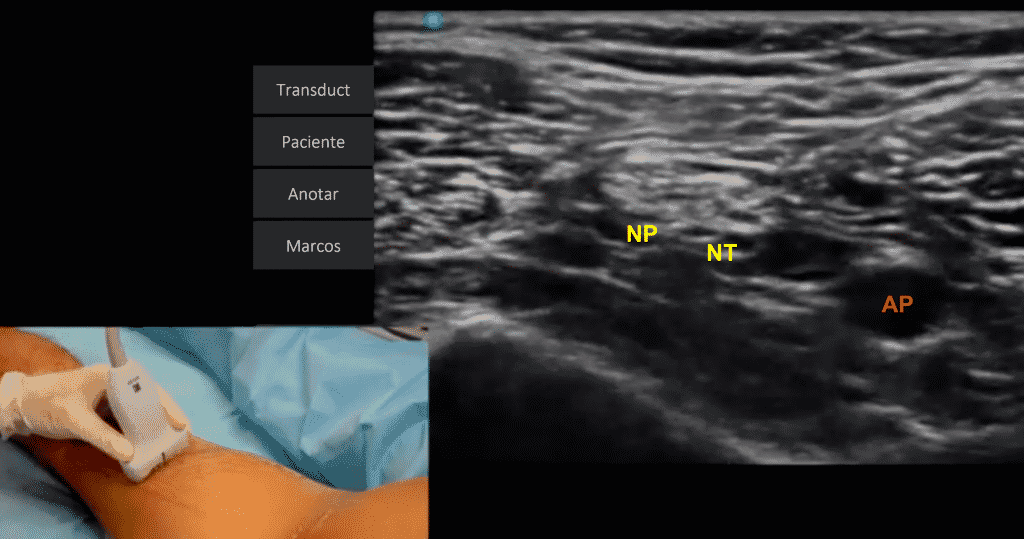

El paciente debe colocarse en decúbito prono, con el anestesista en el lado del miembro a bloquear y el ecógrafo enfrente. Emplearemos una sonda lineal de alta frecuencia y una aguja ecogénica de 80 – 120 mm.

Localización ecográfica: Colocaremos inicialmente la sonda de ultrasonidos en el pliegue poplíteo, tras visualizar ecográficamente la arteria y vena poplíteas como dos estructuras anecoicas, identificaremos los dos componentes del nervio ciático (nervios tibial y peroneo) superficial a los vasos. Inicialmente localizaremos la arteria poplítea y el nervio tibial en intima relación, superficial a ella; posteriormente localizaremos el nervio peroneo, lateral y superficial a la arteria. Al desplazar la sonda ecográfica hacia proximal, hacia el glúteo, visualizaremos como el nervio peroneo y el nervio tibial se unen para formar el tronco común del nervio ciático.

Paciente en posición de decúbito prono que permite localizar mediante una sonda lineal los dos componentes del nervio ciático, los nervios tibial (NT) y peroneo (NP), superficiales en relación a la arteria poplítea (AP).